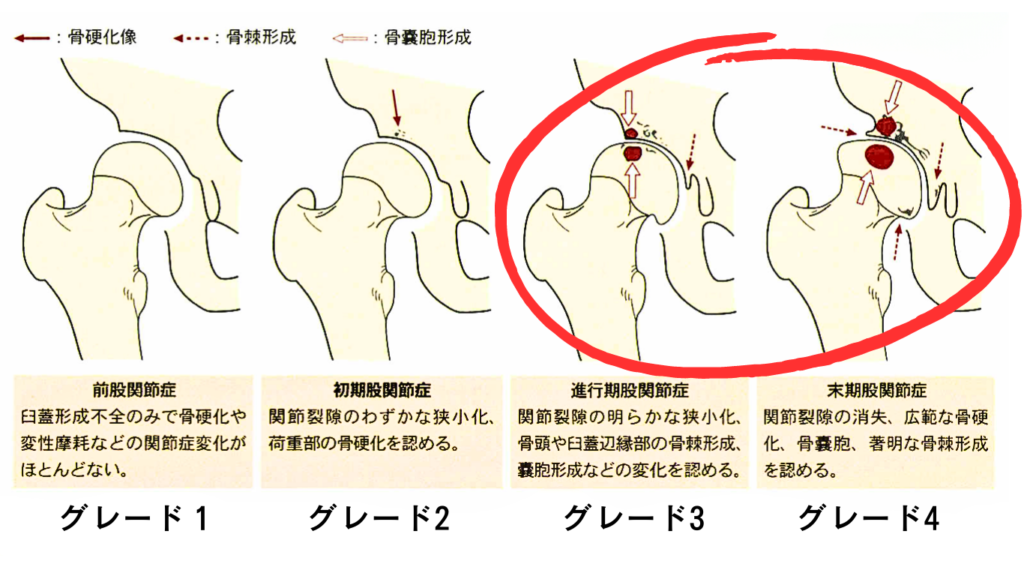

医師は、MRI 検査で変形性関節症の明らかな特徴を認めた場合、症状、身体検査、病歴を精査し、正式な診断を下す可能性があります。

医師は変形性関節症の重症度や段階についても通知します。整形外科医は、MRI で筋肉の緊張や軟骨の断裂などの別の状態を確認することもあります。

MRI では、他の検査よりも早く変形性関節症に関連する変化が示される場合があり、これにより早期に治療を受け、症状の進行を遅らせることができます。場合によっては、手術の予防にもつながる可能性があります。